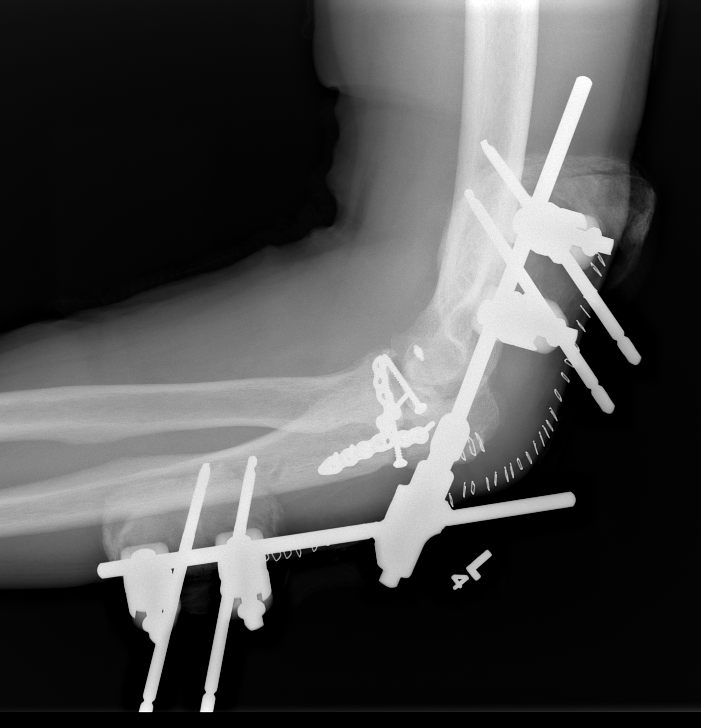

Hinged external fixation

Distal humeral axis

- confirm center of rotation on lateral

- protect ulna nerve

- place guide wire in center of rotation

AO surgery reference hinged external fixator

| Lateral humeral pin | Medial humeral pin | Ulna pins |

|---|---|---|

|

Anterior to radial nerve |

Posterior to ulna nerve |

Subcutaneous border of ulna